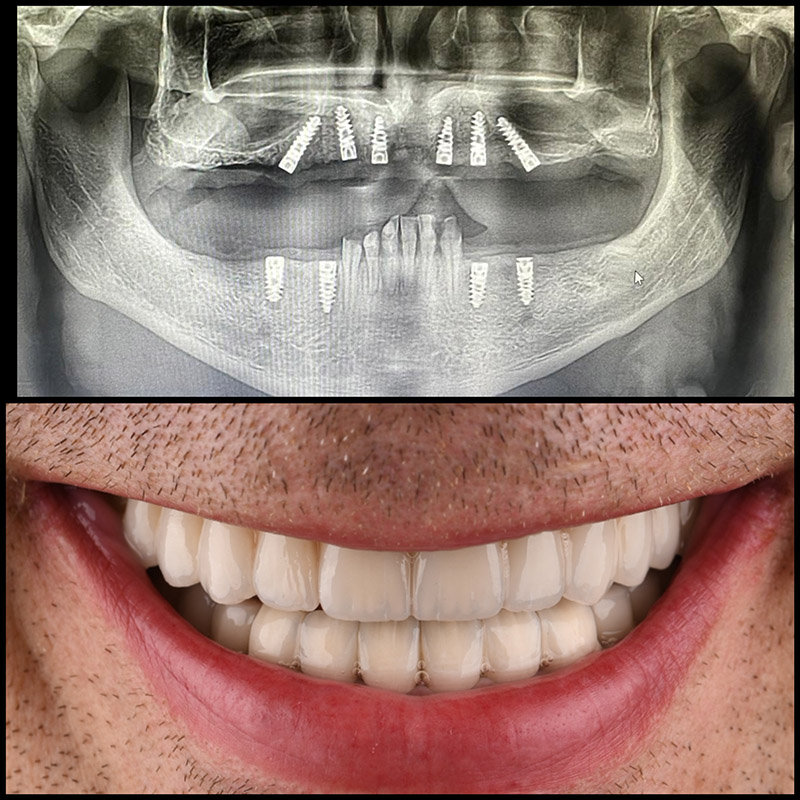

Oralna hirurgija

Oralna hirurgija obuhvata hirurške zahvate u usnoj duplji. Usko je povezana sa drugim granama dentalne medicine, kao što su dentalna protetika i implantologija

Implanti

Dentalni implantati predstavljaju efikasno rešenje za nadoknadu zuba. Vraćaju funkcionalnost, estetski izgled i sposobnost pravilnog govora